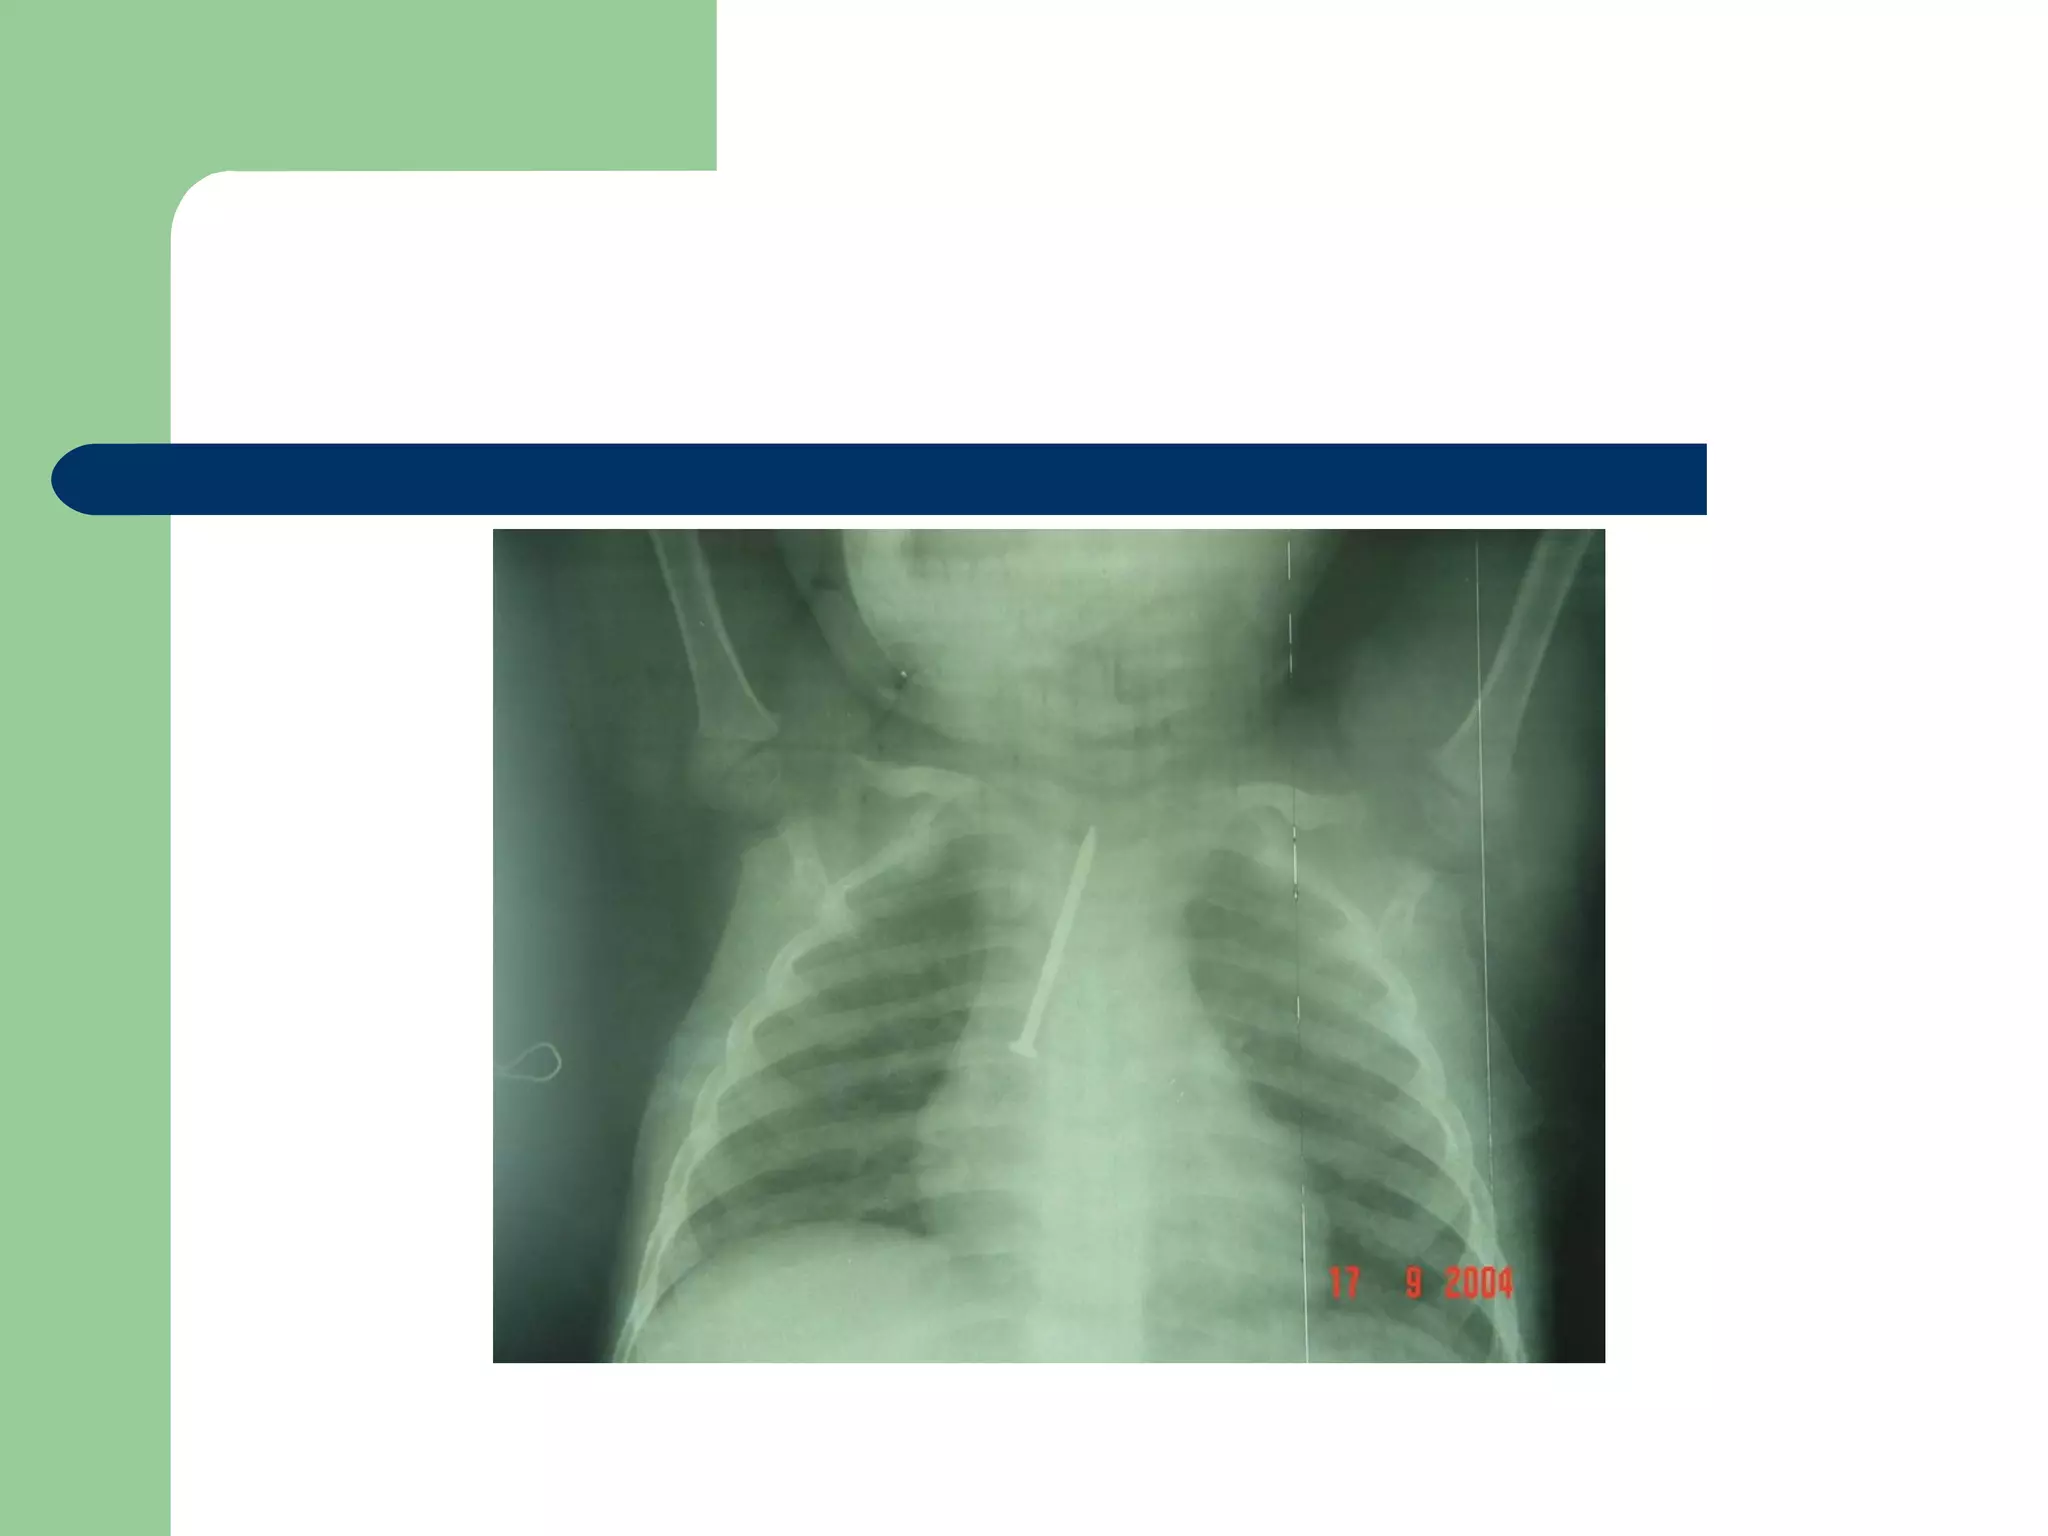

 CXR may be normal if the FB is not radio- opaque.

or it can show a radio- opaque FB such as bone.

A five and a half yr old boy: non-resolved cough

Of 40 days duration

DIAGNOSIS…  Examination:signs of respiratory distress may be present.  CXR may be normal if the FB is not radio- opaque. or it can show a radio- opaque FB such as bone. Obstructive emphysema: is produced by intra-bronchial FB that allows air to enter in inspiration and prevents its exit in expiration. Lung collapse (complete or partial) is produced by a FB that blocks the bronchus completely. Unresolved pneumonic consolidation. Lung abscess or broncheictasis are caused by a long-standing FB.

A five anda half yr old boy: non-resolved cough Of 40 days duration